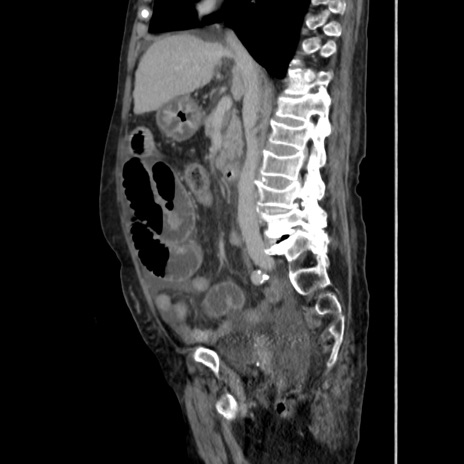

症例31(矢状断像)

【症例】80歳代 女性

【主訴】腹部膨満感

【現病歴】他院にて肝硬変にてフォロー中。1週間前から便秘、腹部膨満感、臍部腫瘤あり受診となる。

【既往歴】肝硬変

【身体所見】腹部膨隆あり、皮膚変化なし、疼痛なし。

【データ】WBC 4600、CRP 0.25